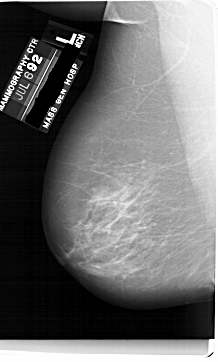

A_1749_1.LEFT_CC

LEFT_CC LINES 6601 PIXELS_PER_LINE 3526 BITS_PER_PIXEL 12 RESOLUTION 43.5 NON_OVERLAY